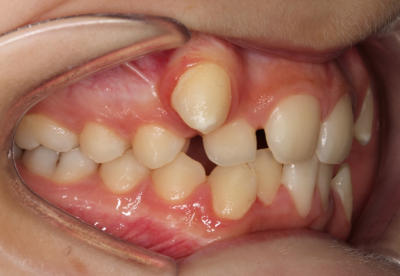

Crowding with lateral open bite – Child case